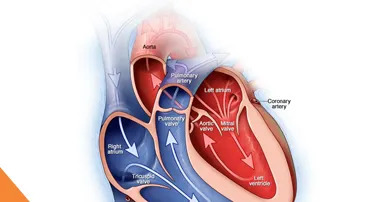

What is the Anatomy of the Heart?

The heart is a muscular, hollow organ that plays a crucial role in the circulatory system by pumping blood throughout the body, supplying oxygen and nutrients to tissues, and removing waste products like carbon dioxide.By learning about what it is and how it works, one can appreciate the role of cardiovascular fitness, and prevent various aspects of heart disease. Here’s a little more about the structure and function of the main parts as well as the chambers, valves, blood vessels, and the electrical system involved in the heart.